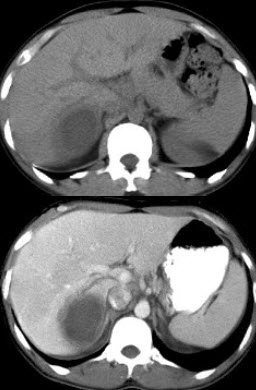

男,63岁,肝区疼痛不适一个月,皮肤巩膜无黄染,AFP高于正常,CT所见如图,最可能的诊断是()

A.肝血管瘤

B.肝转移瘤

C.阿米巴肝脓肿

D.不典型肝癌

E.胆管细胞癌

下列图像的最佳诊断是()

A.阿米巴肝脓肿

B.原发性肝癌

C.肝硬化

D.脂肪肝

E.肝囊肿

90、单项选择题

下列图像最佳诊断是什么()

C.肝转移瘤

D.肝硬化

E.脂肪肝

女,25岁,上腹疼痛不适,低热,有阿米巴痢疾病史,CT检查发现肝右叶低密度病变,如图,最可能的诊断是()

A.原发性肝癌

B.肝血管瘤

C.肝错构瘤

D.阿米巴肝脓肿

E.肝转移瘤